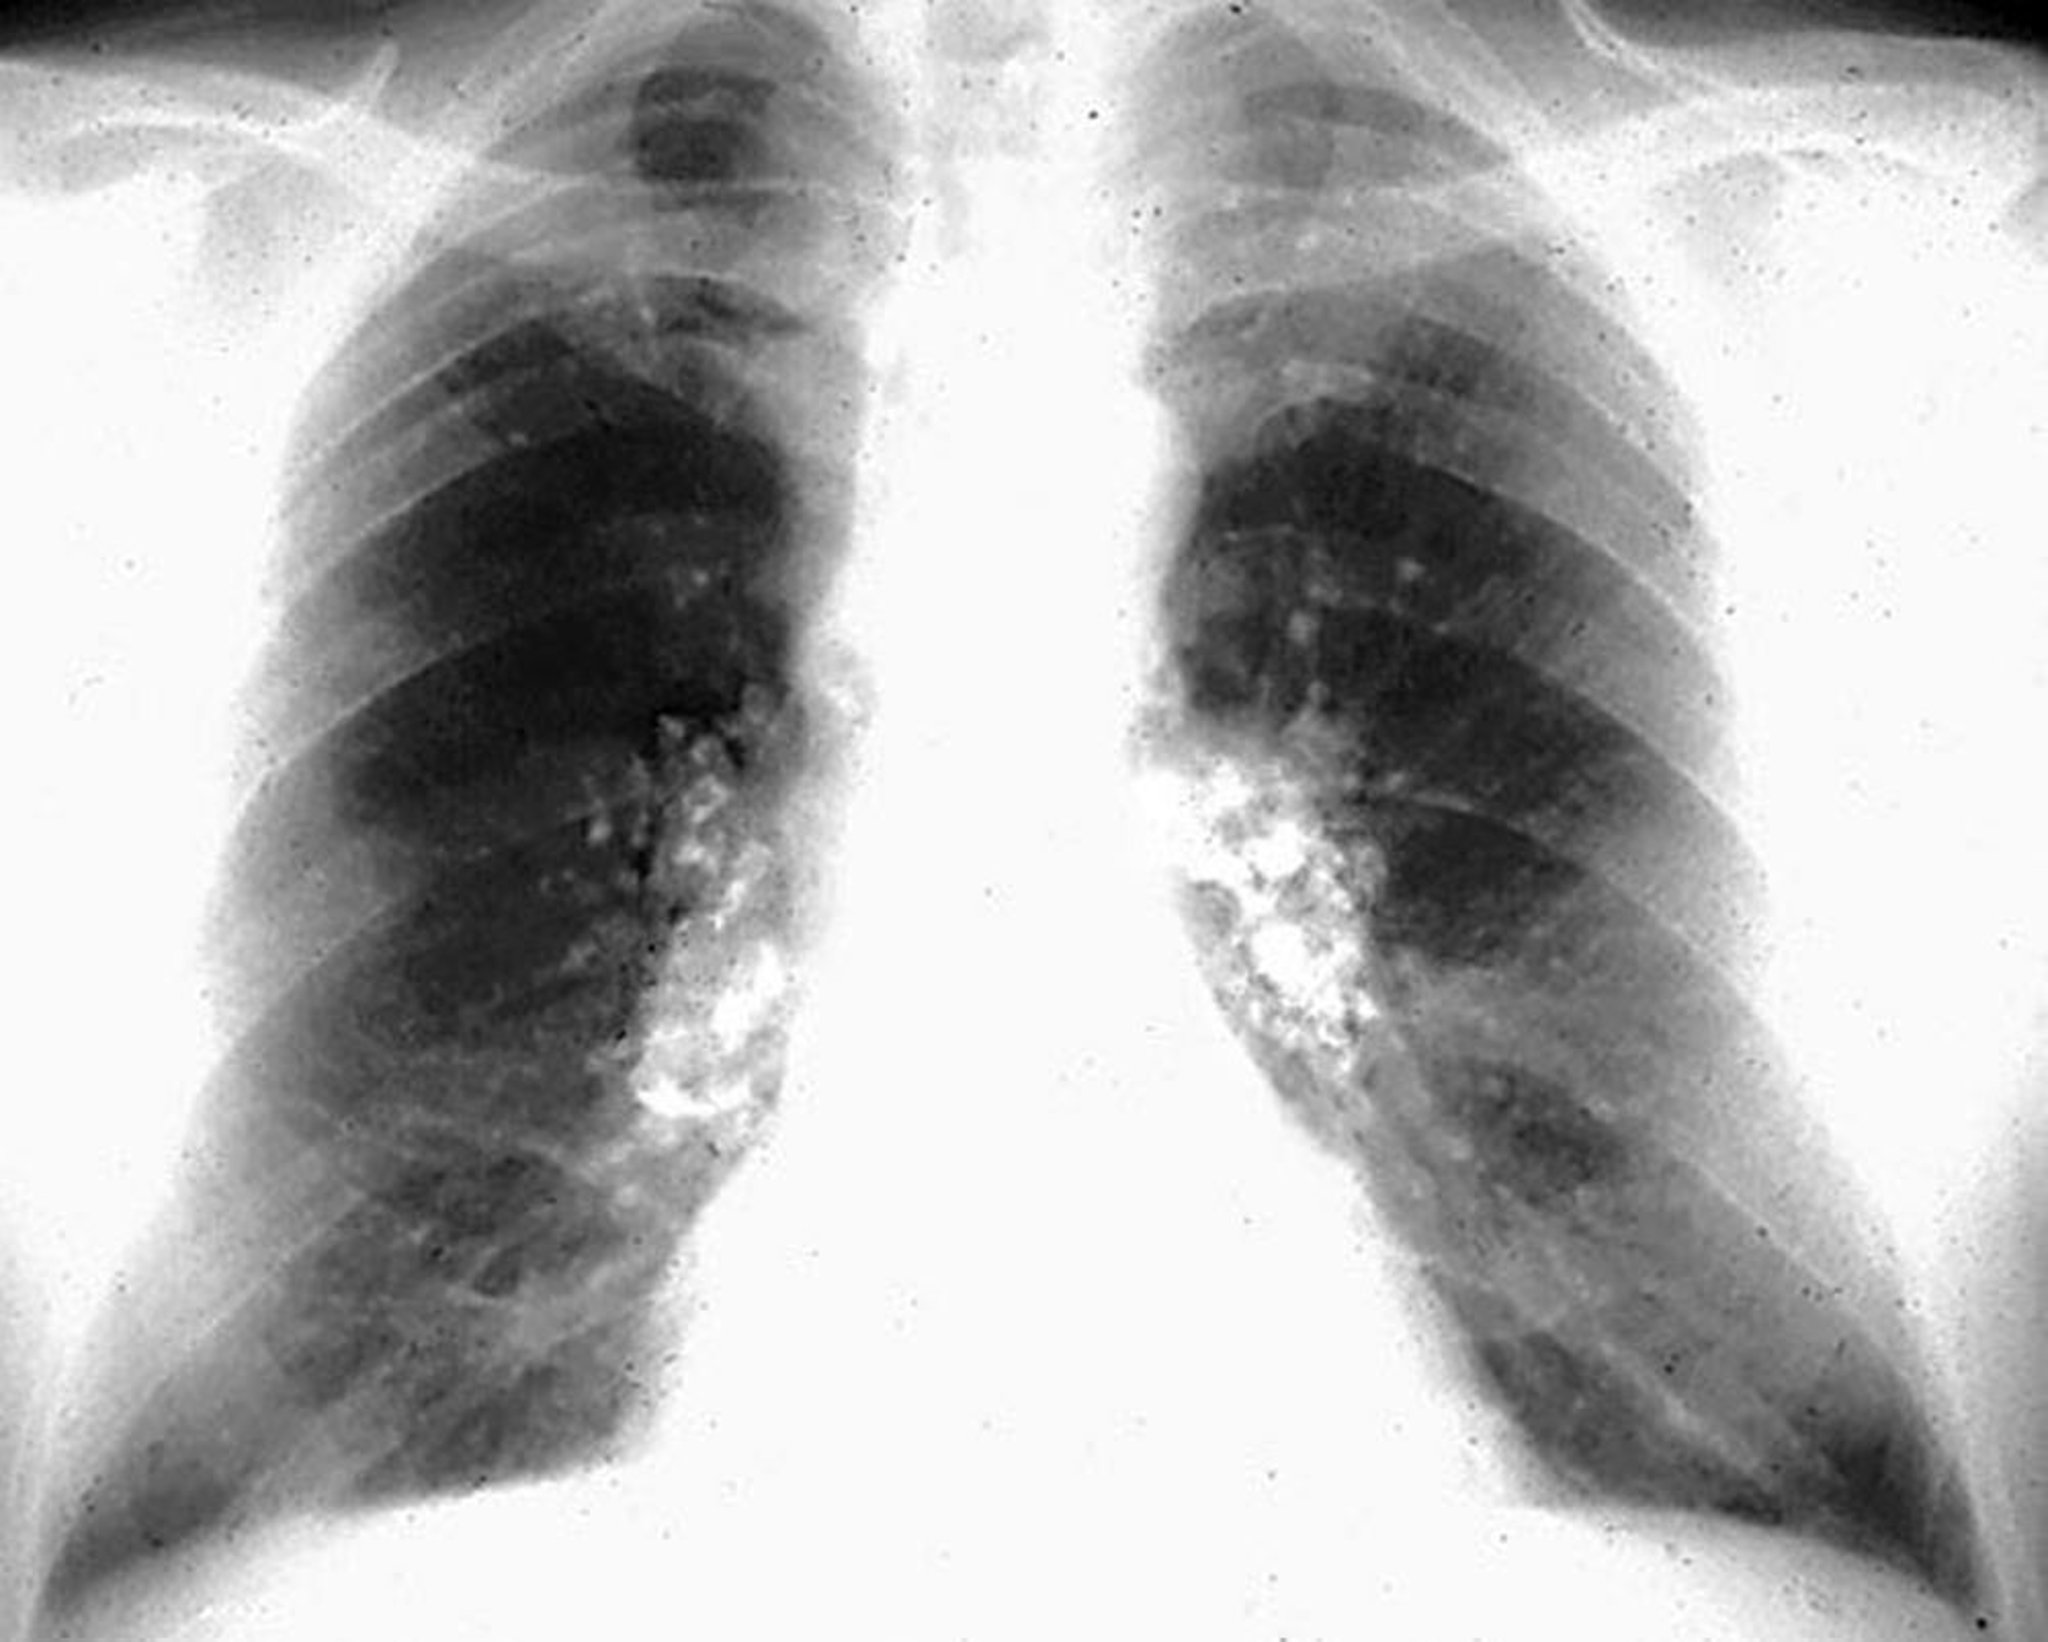

Силикоз — кальцификация по типу яичной скорлупы

Image courtesy of David W. Cugell, MD.

Силикоз